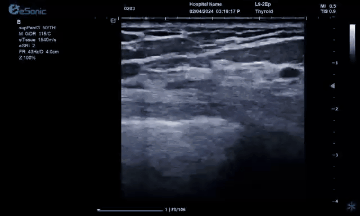

3377体育医疗(ESI)表示,其最新的人工智能功能可以帮助到医疗机构的工作效率,功能包括,实时、动态、快速自动识别病灶,良恶性病灶概率预测,甲状腺结节和乳腺的二维灰阶动态自动实时检测需求,提供多个结节动态检测轮廓框。实时获取多幅具备临床特征(大小、属性等)的结节切面,同时提供当前切面所示结节的结节大小、属性特征、TI-RADS 分级。

对于甲状腺结节相关的自动检测功能,甲状腺结节病灶检出率≥95%,良恶性分类灵敏度≥90%、良恶性分类特异度≥85%。